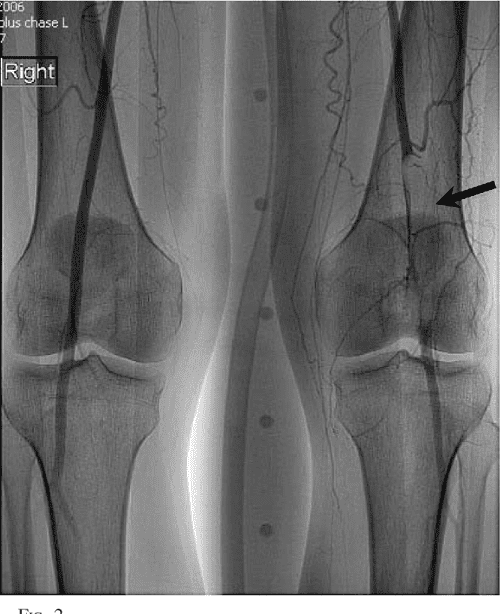

From www.semanticscholar.org

Figure 1 from HighPressure Water Jet Injury to the Neck and Arm Semantic Scholar Jet Injection Injuries Jugpal s arneja, md, mba, frcsc; Hydraulic injection injury occurs when a jet of fluid under pressure penetrates the skin of an individual, often from a momentary. H igh pressure injection injuries are defined as puncturing of the dermis by a jet of fluid or air under pressure. In cases involving clean water and air injuries, good functional outcomes may. Jet Injection Injuries.